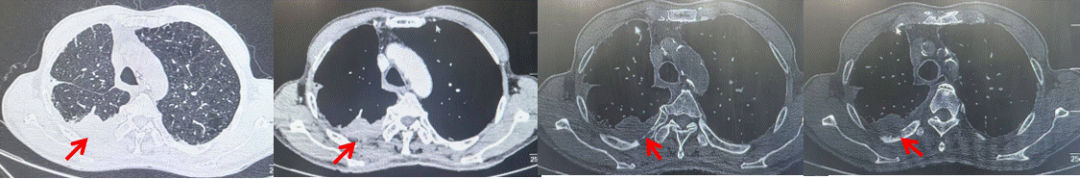

69岁男性,无糖尿病、高血压、心脏病等基础疾病,无吸烟、饮酒史,无肿瘤家族史。2023.06.07行胸部CT检查:右肺上叶胸膜下见肿物影,大小约33mm×22mm,边缘可见分叶,考虑恶性病变可能性大,双肺间质改变(如图1)。2023.06.14行“单孔胸腔镜下右肺上叶切除、肺门及纵隔淋巴结清扫、胸膜粘连松解术”;术后病理:(右肺上叶)腺癌(低分化,实体型占60%,不良腺体占40%),局灶伴神经内分泌标记表达(CD56、Syn),可见STAS及胸膜侵犯,未见确切神经侵犯及脉管内癌栓;(气管切缘)净;(淋巴结)未见转移癌0/26(2组0/2;4组0/6;7组0/2;对侧7组0/8;10组0/2;11组0/3;12组0/2;13组0/1)。术后分期pT2aN0M0 IB期,术后NGS基因检测:无驱动基因突变,PD-L1(22C3)TPS<1%。术后定期复查。

图1:患者手术前(2023.06)胸部CT肺窗及纵隔窗

图2:患者胸膜及肋骨转移(2024.11)胸部CT肺窗、纵隔窗及骨窗

图3:患者免疫联合化疗治疗后胸部CT,(A、B)图展示信迪利单抗联合培美曲塞+卡铂治疗

4周期(2025.02)疗效,(C、D)图展示信迪利单抗+培美曲塞维持治疗6周期(2025.07)疗效